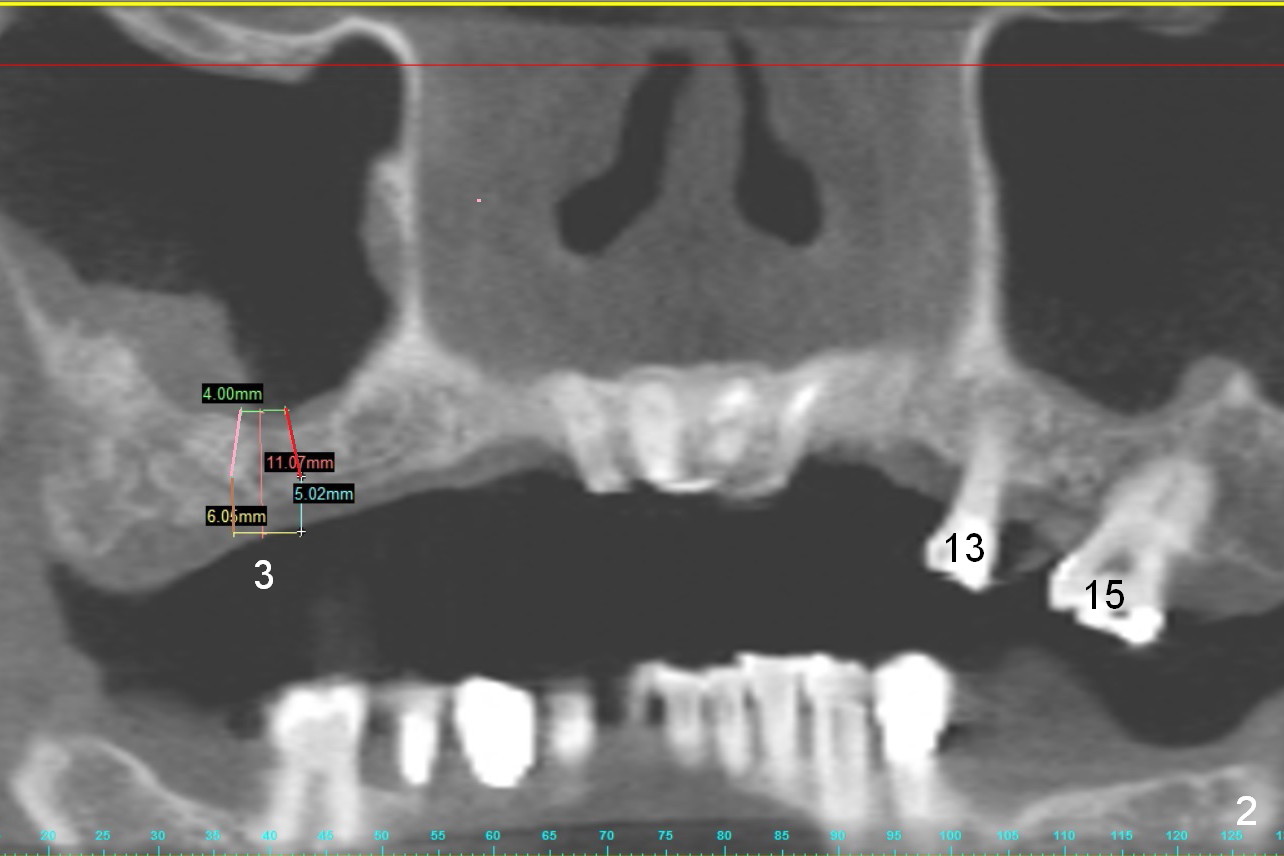

A 68-year-old lady has several missing teeth (Fig.1,2).  She has agreed to have an implant at the site of #3 (Fig.3) to stabilize an upper removable partial denture (RPD).  The latter will be more stable if an extra implant is placed at #6 (Fig.1,2,6).  There is enough bone to place implants at #4,5 (Fig.4,5).  Bone density at these sites is low.  Osteotomy should be underprep with bone condensation.  Edentulous space is high so long abutments are required (9 mm instead of 3 or 5 mm (regularly used)).  Angled abutments should be prepared.